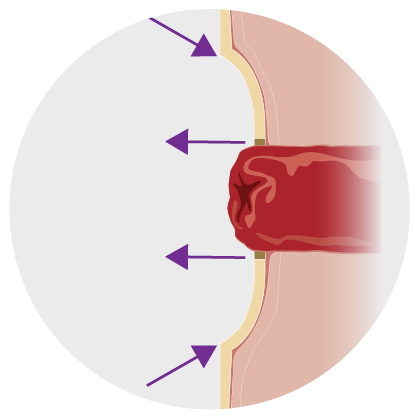

How convexity pouch systems work with a flush or retracted stoma¹

1.Position theskin barrier above a flushstoma. This also works with retracted stomas or with skin folds. |

2.The convex skin barrier exerts downwards pressure on the skin. |

3.The pressure on the peristomal skin will help the stoma protrude further into the pouch, allowing for a better seal and helping to. |